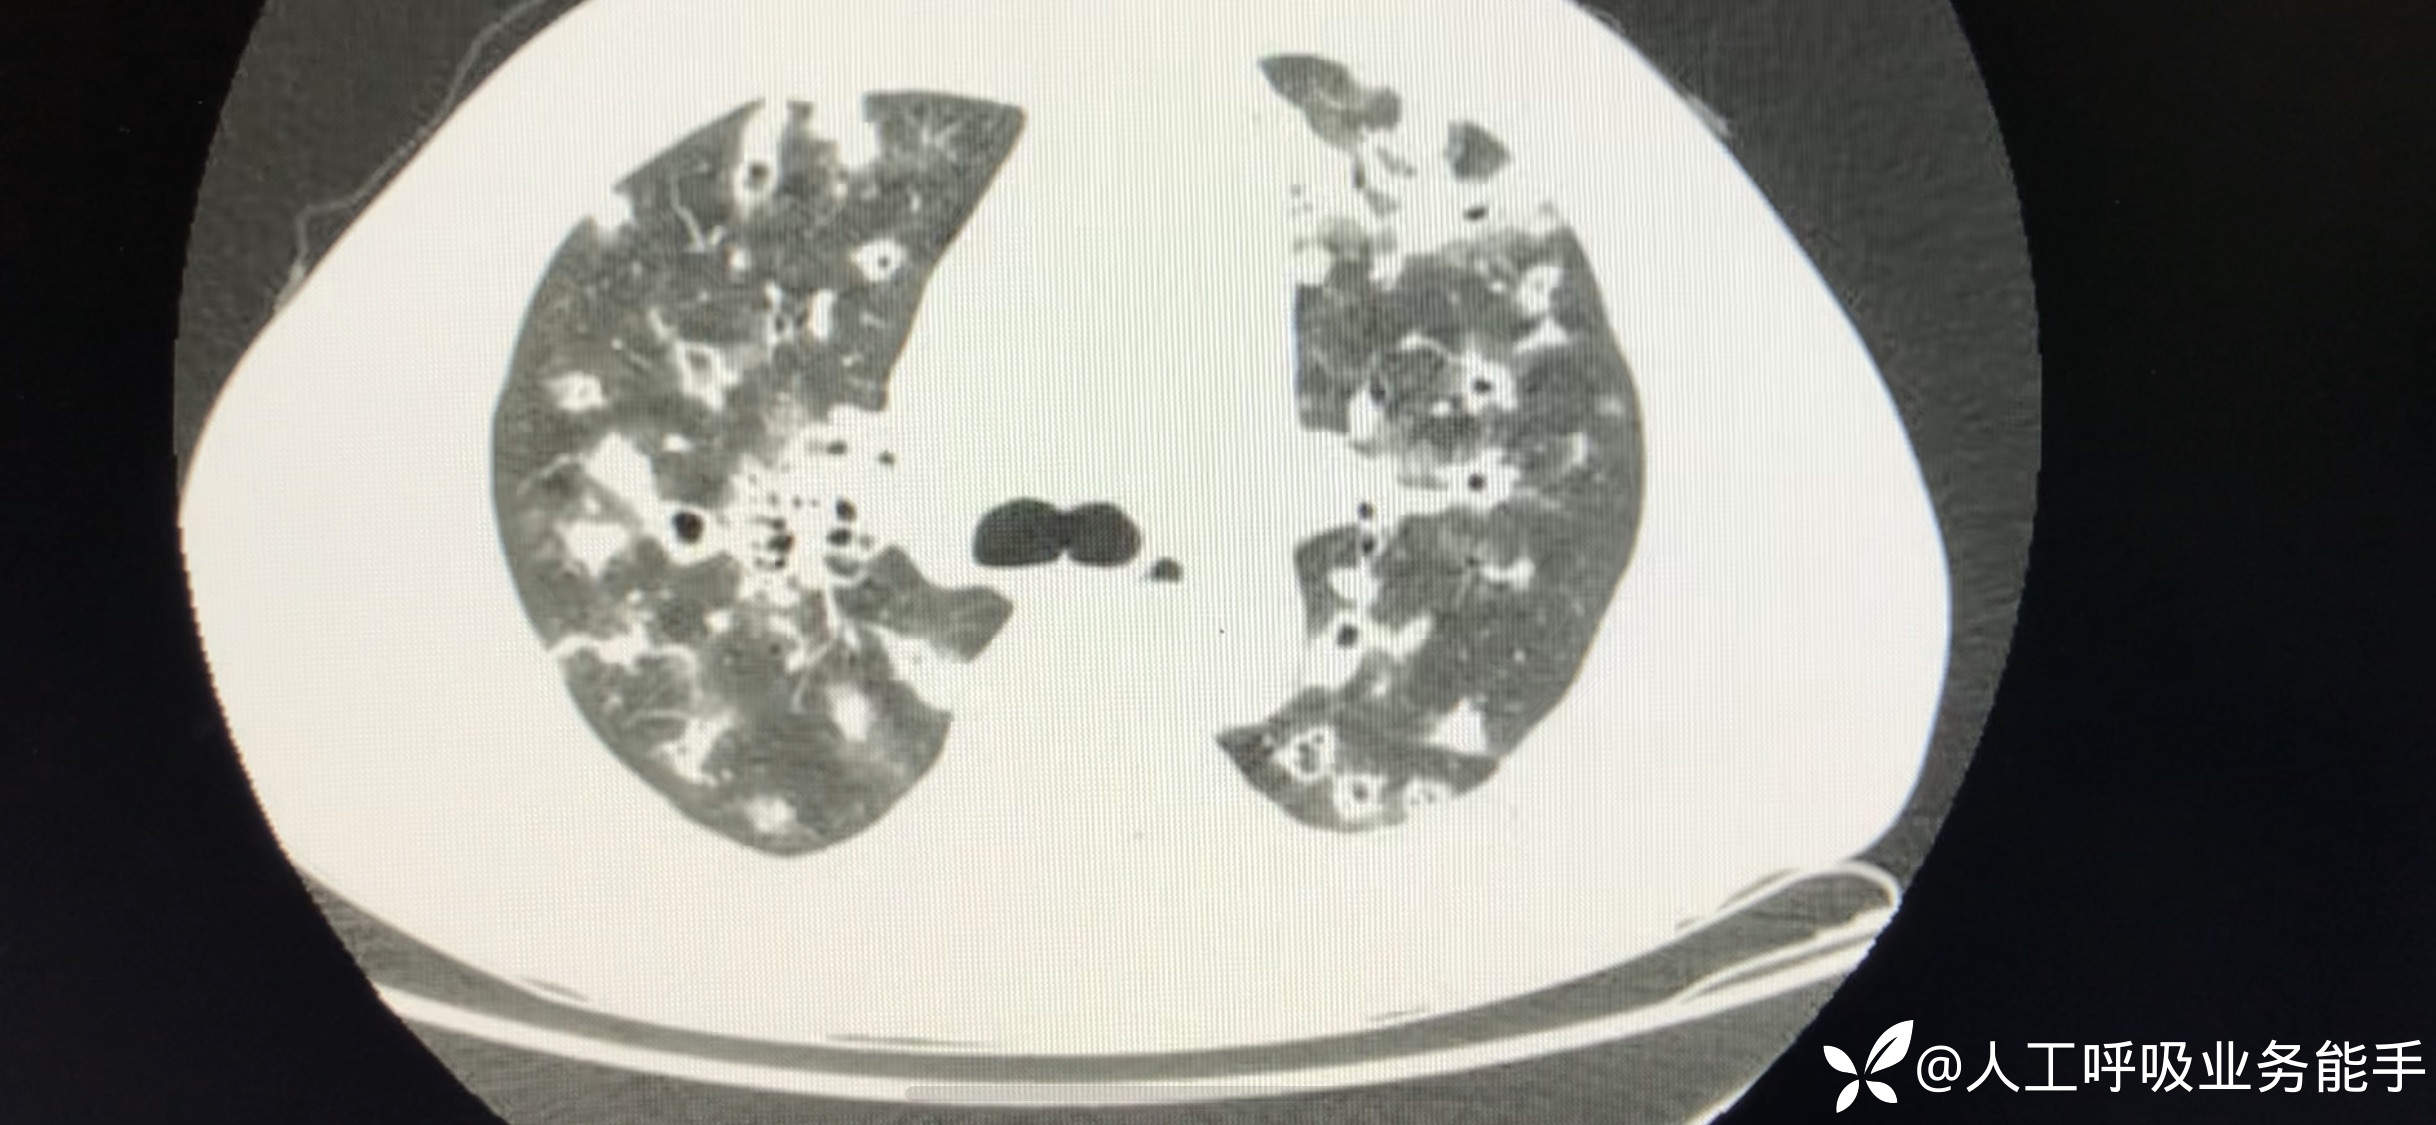

初诊影像: